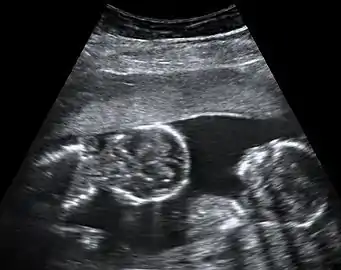

By performing an obstetric ultrasound at a gestational age of 10–14 weeks, monochorionic-diamniotic twins are discerned from dichorionic twins. The presence of a "T-sign" at the inter-twin membrane-placental junction is indicative of monochorionic-diamniotic twins (that is, the junction between the inter-twin membrane and the external rim forms a right angle), whereas dichorionic twins present with a "lambda (λ) sign" (that is, the chorion forms a wedge-shaped protrusion into the inter-twin space, creating a rather curved junction).[4] The "lambda sign" is also called the "twin peak sign". At ultrasound at a gestational age of 16–20 weeks, the "lambda sign" is indicative of dichorionicity but its absence does not exclude it.[5]

In contrast, the placentas may be overlapping for dichorionic twins, making it hard to distinguish them, making it difficult to discern mono- or dichorionic twins on solely the appearance of the placentas on ultrasound.